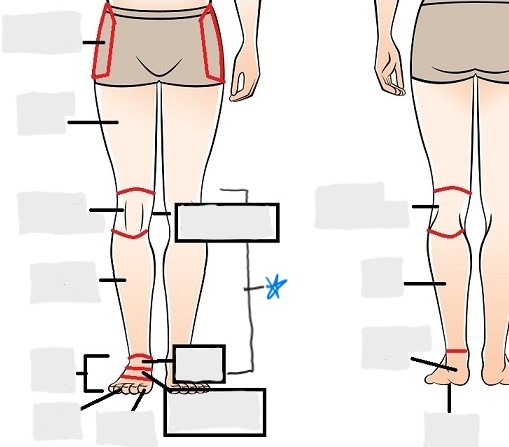

axial

appendicular

coxal

femoral

patellar

popliteal

crural

sural

peroneal

calcaneal

plantar